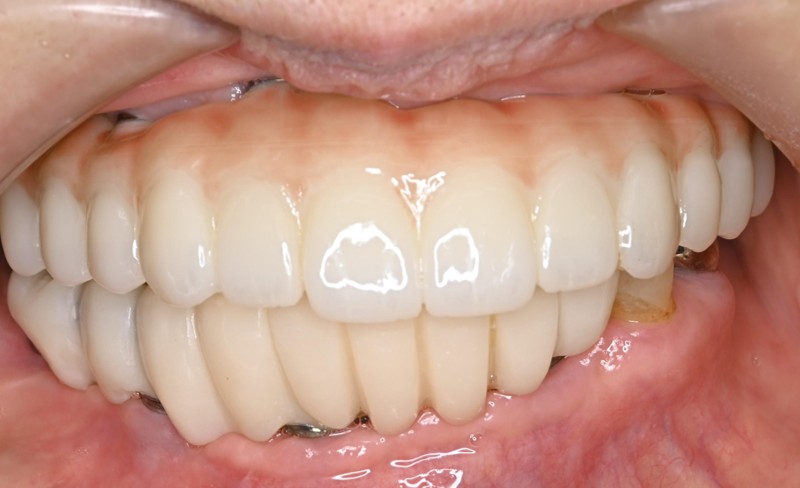

Before

After